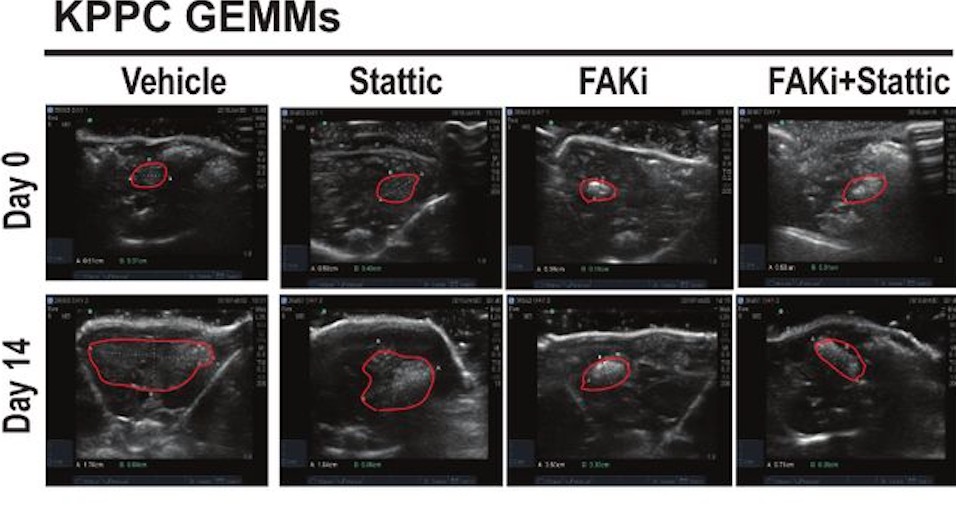

Development of resistance to FAK inhibition in pancreatic cancer is linked to stromal depletion

doi:10.1136/gutjnl-2018-317424

Targeting focal adhesion kinase renders pancreatic cancers responsive to checkpoint immunotherapy

doi:10.1038/nm.4123